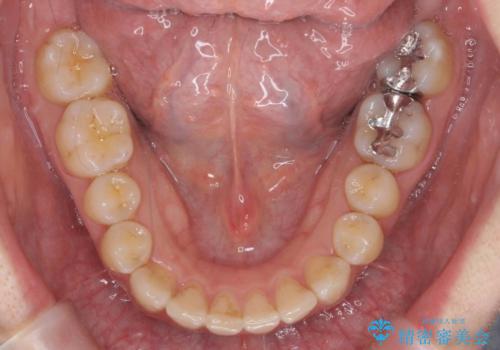

- 前歯のがたつきとガミースマイルの改善を希望して来院。

ガミーは非常に軽度でひどくはなかったのですが、改善を強く希望されていました。

上の前歯をひっぱりあげて目立たなくするために、上の前歯のワイヤー部分矯正を行い、ミニスクリューからわずかに引っ張り上げました。

また、右上の犬歯の反対咬合についてもワイヤー矯正で短期間で改善することができました。

前歯の過蓋咬合についても改善しています。